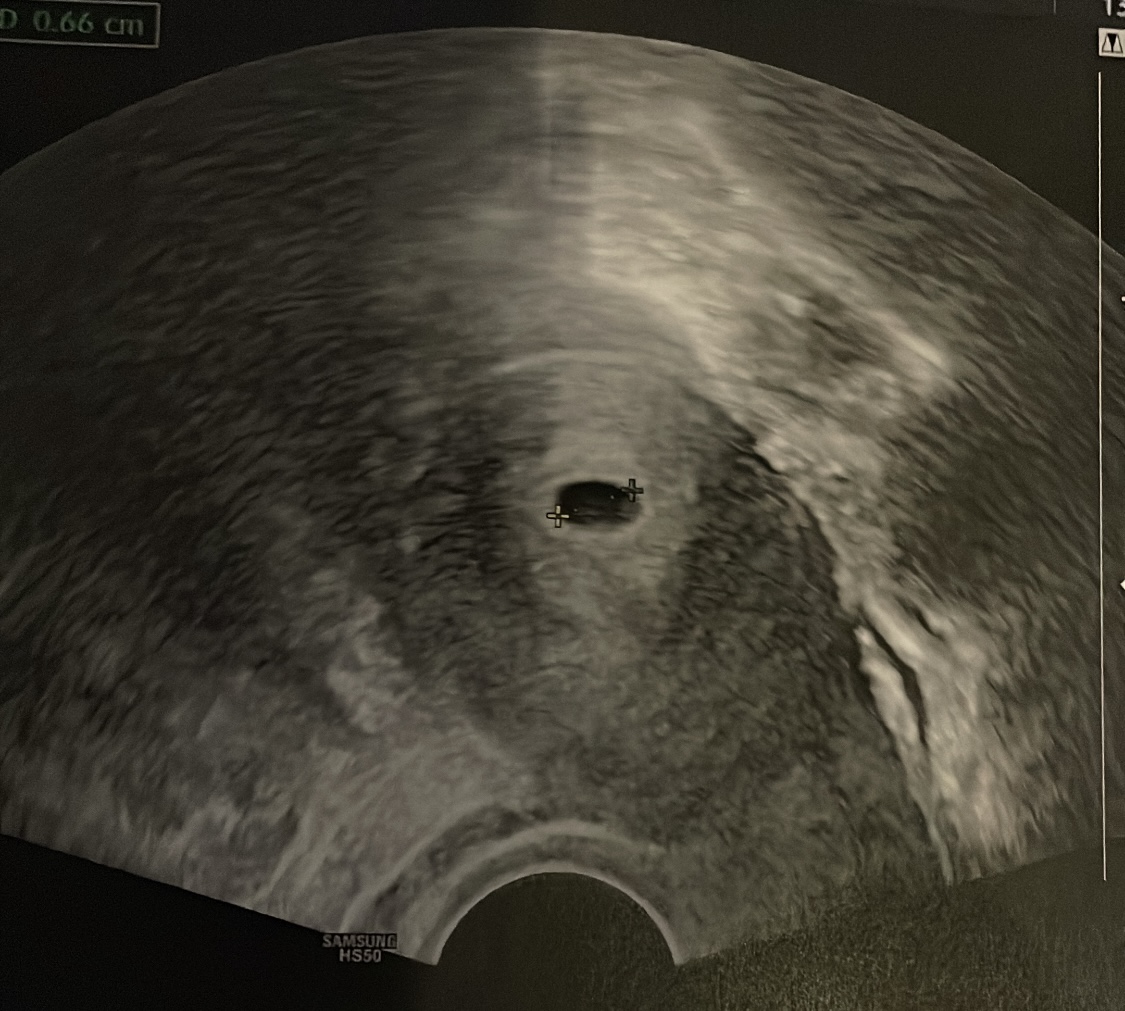

Da ist unser Wurm ! 3,2 mm klein. Das Herz hat ordentlich geschlagen. Hach ich bin verliebt. Nächste Woche ist der nächste Termin beim Frauenarzt. Ich bin offiziell entlassen von der Klinik aus. Endlichhhhh. Ich freu mich so. Ich war aber heut so super genervt, da ich mal wieder fast 2 std warten musste und meine Laune dann naja im Keller war.

Das schlagen des herzes machte aber wieder alles gut ❤️ danke, dass ich so ein Wunder nochmal erleben darf

Heut seht ihr die fruchthöhle und unten rechts im Eck lässt sich der Dottersack vermuten

Gestern war ich bei 5+1.

Nächsten Donnerstag sollte man dann schon mehr sehen 🥰